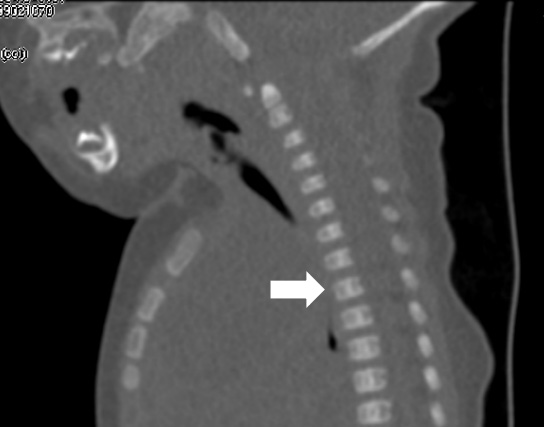

纵隔巨大淋巴管畸形压迫气管影响呼吸